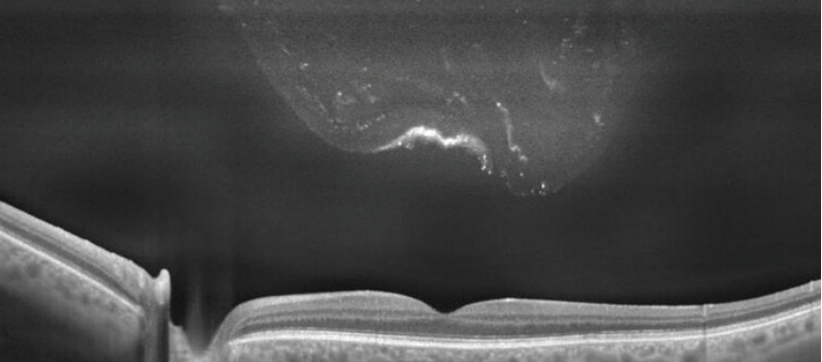

Although floaters are typically clinically inconsequential, a small subset of patients have debilitating symptoms that interfere with their vision and require treatment #ophthalmology buff.ly/2KZJmlB